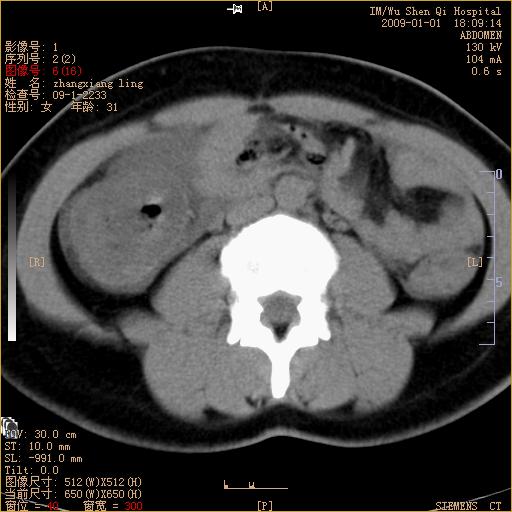

标题: CT17527:F31Y,腹痛伴血便9小时 [打印本页]

标题: CT17527:F31Y,腹痛伴血便9小时

升结肠肠壁不规则增厚,肠腔狭窄,考虑升结肠占位,建议增强扫描

升结肠肠壁不规则增厚,肠腔狭窄,考虑升结肠占位,建议增强扫描,不除外肠套叠.

升结肠肠壁不规则增厚,似呈同心圆改变,其有积液。结合病史首先考虑肠套叠伴肠壁坏死可能性大,结肠肿瘤待排。

升结肠肠壁不规则增厚,似呈同心圆改变,其有积液。结合病史首先考虑肠套叠伴肠壁坏死可能性大,结肠肿瘤待排。支持!(发病急,无过去史,应首先考虑:肠套叠)

患者已手术,结果肠系膜血栓形成肠坏死

患者已手术,结果肠系膜血栓形成肠坏死。

结合病史并看到升结肠增粗及局限的腹腔积液,考虑肠套叠伴肠壁坏死可能性大

结果:患者已手术,结果肠系膜血栓形成肠坏死。回过头再看局部肠壁增厚有分层(高密度坏死及低密度水肿)表现。